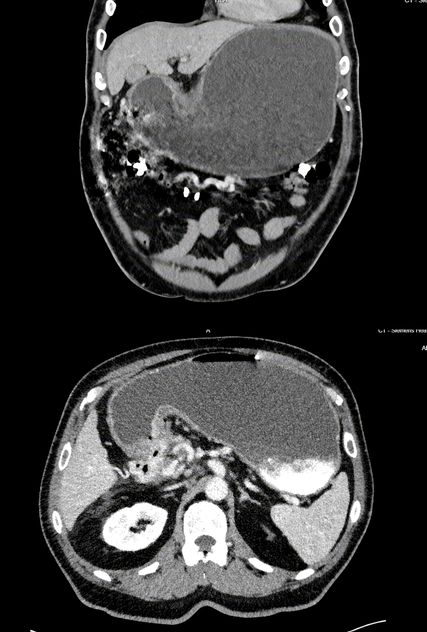

Abb. 1 und 2: Computertomografie Abdomen: massiv dilatierter Magen mit Kalibersprung am Pylorus und tumoröser Infiltration ausgehend vom Pankreaskopf

Gastroskopisch zeigte sich das Bild einer Refluxösophagitis Grad D, wobei als auffallendster Befund größere Speisereste im Magen imponierten. Das Antrum zeigte sich, soweit beurteilbar, verquollen, womit sich insgesamt der Verdacht auf eine Magenausgangsstenose ergab. In routinemäßig entnommenen Gewebeproben aus Antrum und Corpus des Magens zeigte sich histologisch eine geringgradige Gastritis (Typ C) ohne Nachweis von Helicobacter pylori. In einer weiterführend veranlassten kontrastmittelgestützten CT-Untersuchung zeigte sich ein massiv dilatierter Magen mit Spiegelbildung und Kalibersprung im Bereich des Pylorus. Die Magenwand war bis zu 2cm verdickt und nicht eindeutig vom Pankreaskopf abgrenzbar (Abb.1 und 2). Es zeigte sich eine wohl vom Pankreaskopf ausgehende, schwer vermessbare, den Pylorus infiltrierende weichteildichte Raumforderung mit Umscheidung der Arteria hepatica propria und ihrer Aufgabelung im Bereich der Leberpforte. Der Pankreasschwanz war hochgradig atrophiert, der Ductus pancreaticus mit 6mm erweitert. Womit sich insgesamt ein hochgradig suspekter Befund für ein Pankreaskarzinom ergab.